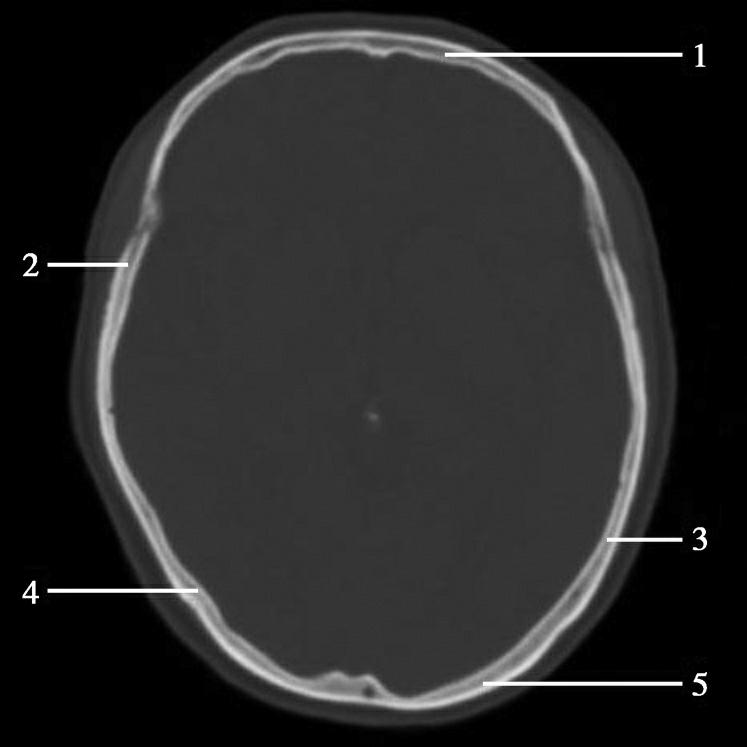

重要结构:中央沟、额叶、顶叶、中央旁小叶、中央前回、中央后回(图1-2-46~图1-2-48)。

图1-2-46 中央旁小叶下部层面

A.横断面;B.横断面标注

1.上矢状窦;2.大脑镰;3.额叶;4.中央前沟;5.中央前回;6.中央沟;7.中央后回;8.中央后沟;9.中央旁小叶;10.缘上回;11.角回;12.顶上小叶;13.楔前叶

图1-2-47 中央旁小叶下部层面(骨窗)

1.额骨;2.冠状缝;3.顶骨;4.人字缝;5.枕骨

此层面通过扣带沟上方的中央旁小叶,位于大脑镰两侧中部偏后,其前方为额内侧回,后方为楔前叶及楔叶,外侧为两半球的放射冠,放射冠的外侧可见中央沟及中央前、后回,中央沟仍位于大脑凸面中部,常为大脑半球外侧面三条较深脑沟中的中间一条。中央前回的前方为额上回、额中回。断面后部内侧为楔前叶及顶上小叶,此叶外侧为角回,角回前外侧为缘上回。此层面已无枕叶。大脑镰位居中线,其前、后端可见上矢状窦断面。